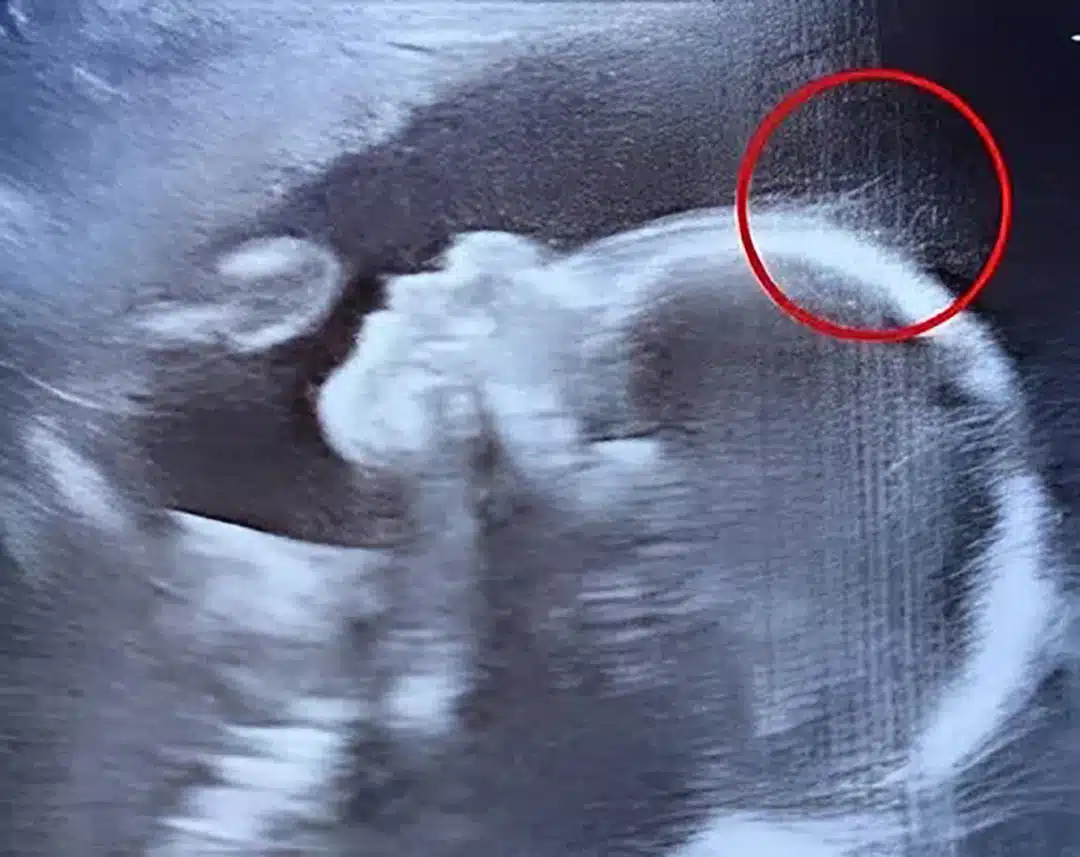

Lors de son examen de routine, une technicienne remarque quelque chose d'insolite sur l'écran : une petite silhouette avec ce qui semble être... des cheveux ? Ce détail charmant n'était que le prélude d'une incroyable surprise qui allait émerveiller toute une équipe médicale.